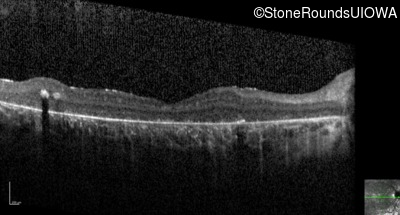

Optical Coherence Tomography - Left - 5/225 sc

Exemplar / OCT Stack